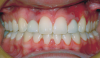

Fig 2. Patient was missing teeth Nos. 7 and 10 (Fig 1). Canine substitution was the treatment used to replace these missing teeth (Fig 2).

Canine substitution can be an excellent alternative for the replacement of the missing maxillary lateral incisor (Figure 1 and Figure 2). This treatment option can be particularly effective if the canine has a flat facial surface, is not too wide mesiodistally, and has a color similar to the contralateral lateral incisor. Patients with missing lateral incisors who present with maxillary dentoalveolar protrusion and/or an Angle class II molar relationship and minimal crowding in the mandibular arch are considered excellent candidates for canine substitution.7